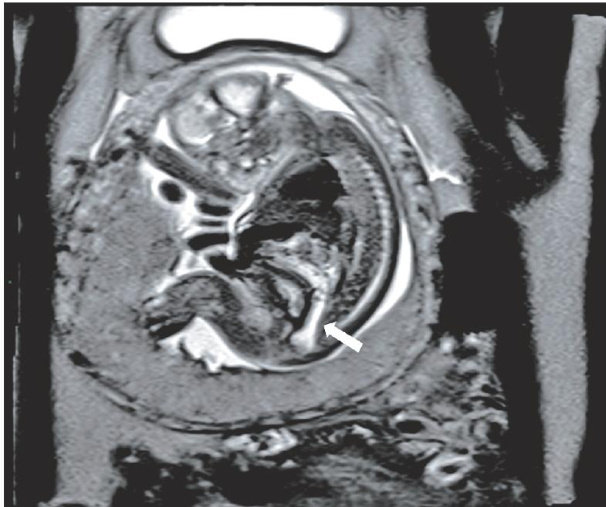

摘要目的应用经胸超声心动图(TTE)测量功能性二尖瓣反流(FMR)患者经导管二尖瓣缘对缘修复术(TEER)相关解剖参数,探讨其在评估TEER解剖适应证中的临床价值。方法选取我院经TTE初诊为FMR的患者220例,应用TTE、经食管超声心动图(TEE)分别获取患者TEER相关解剖参数,包括前瓣长度(ALL)、后瓣长度(PLL)、二尖瓣口面积(MVA)对合长度(CL)对合高度(CH)、房间隔总长(IAS),比较二者测值的差异;分别采用Pearson相关分析法和组内相关系数(ICC)分析TTE与TEE测值的相关性和一致性。以TEE分区结果为金标准,分析TTE在评估"绿区-黄区-红区"解剖适应证分类中的诊断效能。采用ICC评估TTE测量TEER相关解剖参数在观察者内及观察者间的一致性。结果TTE测量的MVA、CH、CD均高于TEE测值,差异均有统计学意义(均 P<0.05 );TTE与TEE测量的AML、PML、IAS比较差异均无统计学意义。TTE与TEE测量的ALL、PLL、MVA、CH、IAS均表现出高度相关 (r=0.864,0.833,0.955,0.896, 0.967,均 P<0.001 )及良好一致性 (ICC=0.862,0.831,0.936,0.884,0.967, 均 P<0.001 ),CL表现出中度相关 (r=0.569,P<0.001 )及较差一致性 (ICC=0.422,P<0.001) 。TTE评估FMR患者TEER三分区解剖适应证的整体准确率为 88.6% ,评估"绿区”的灵敏度、特异度、准确率分别为 98.3%.62.5%.90.5% ,评估“黄区"的灵敏度、特异度、准确率分别为 45.5% 、 96.3% 、86.6% ,评估"红区"的灵敏度、特异度、准确率分别为 73.3%.100% 98.2%。TTE测量的ALL、PLL、MVA、CL、CH、IAS在观察者内ICC分别为 0.834,0.839,0.978,0.430,0.842,0.987 (均 P<0.001 ),在观察者间ICC分别为 0.790,0.983,0.976 0.430、0.789、0.982(均 P<0.001 ),表明ALL、PLL、MVA、 CH 、IAS在观察者内及观察者间的一致性均良好,CL的一致性较差。结论TE在评估FMR患者“绿区-黄区-红区"TEER